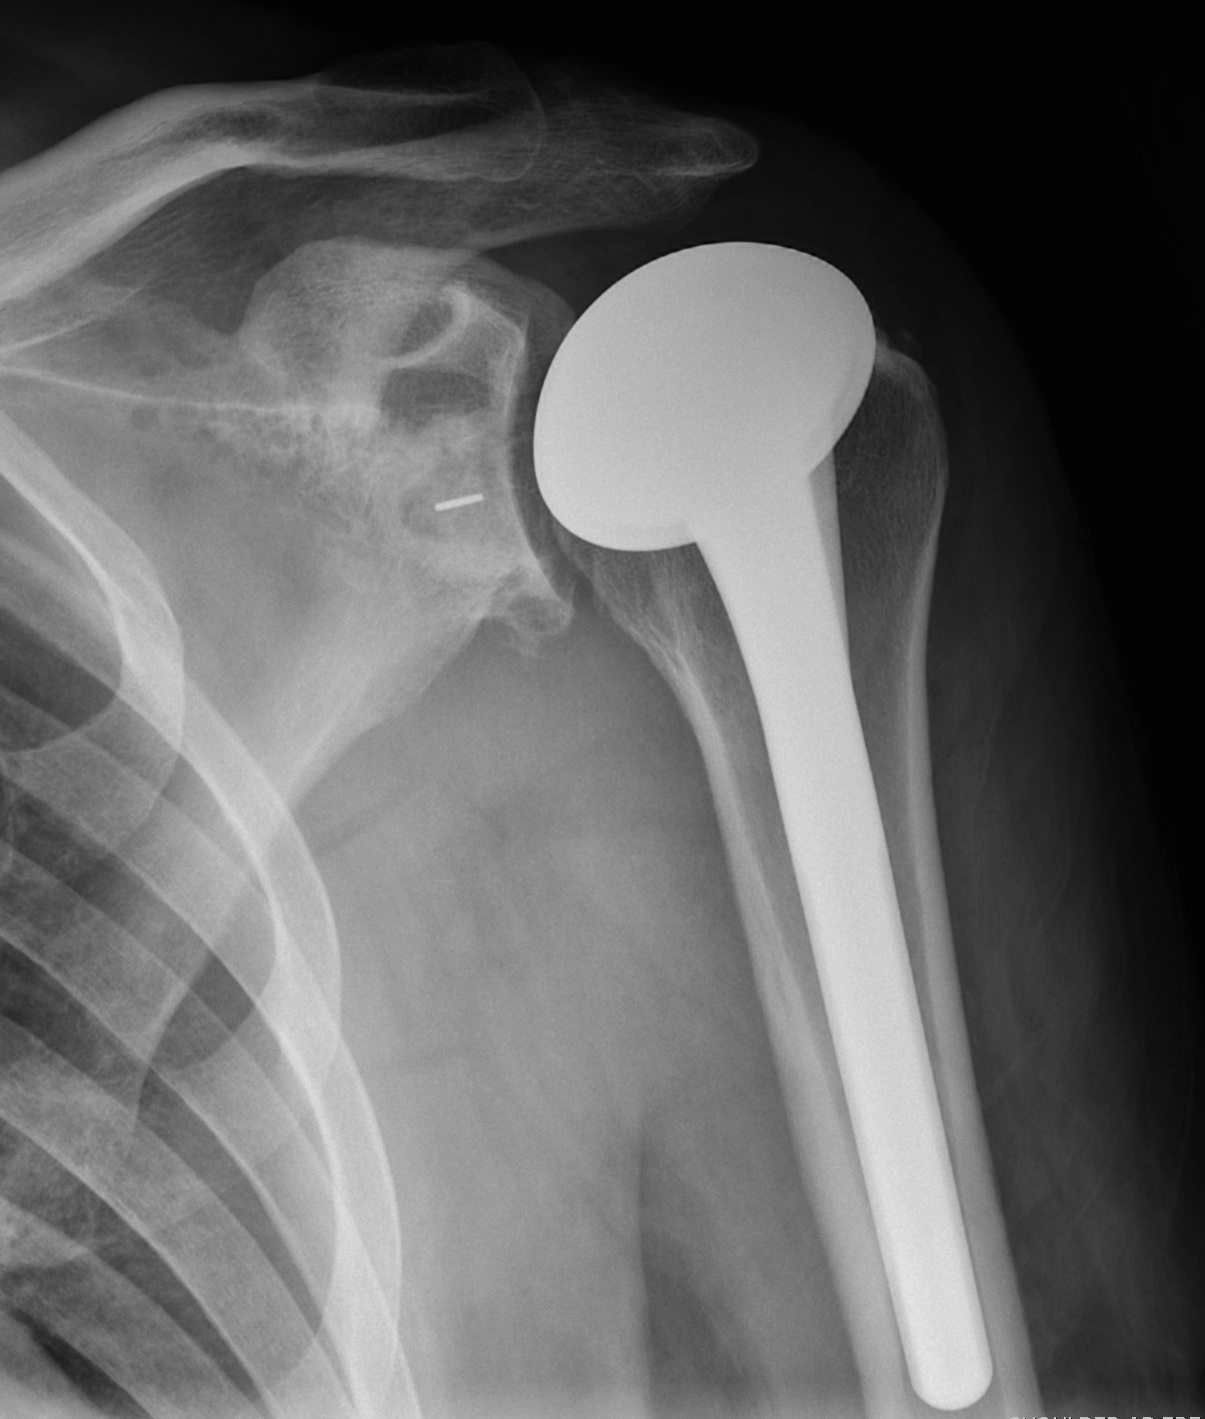

Technique

- extra-articular

Portals

- posterior portal very lateral so can see anterior aspect subacromial space

- port of Wilminton at anterolateral acromion to access SSC

- anterior portal in normal position, slightly more lateral so becomes working portal

Engaging Hill Sachs

- head that translates 50% in all directions

- allows 30o ER with arm at side

- stable posteriorly